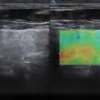

DW-L50 Exp

DW-L50 Exp

Aparato de Diagnóstico Ultrasónico Digital a Color Completo de Tipo Laptop

El DW-L50 Exp, impulsado por la avanzada plataforma de ultrasonido ST-U, ofrece imágenes ultra claras en todo momento. Con una movilidad y adaptabilidad sobresalientes, funciona de manera fiable en diversos entornos clínicos complejos. Su introducción permite que más instituciones médicas accedan a tecnología de ultrasonido rentable y de alto rendimiento.